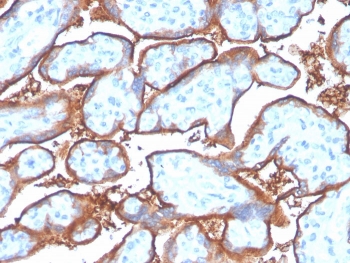

IHC staining of FFPE human placenta with recombinant PD-L1 antibody (clone PDL1/4280R). HIER: boil tissue sections in pH 9 10mM Tris with 1mM EDTA for 20 min and allow to cool before testing.